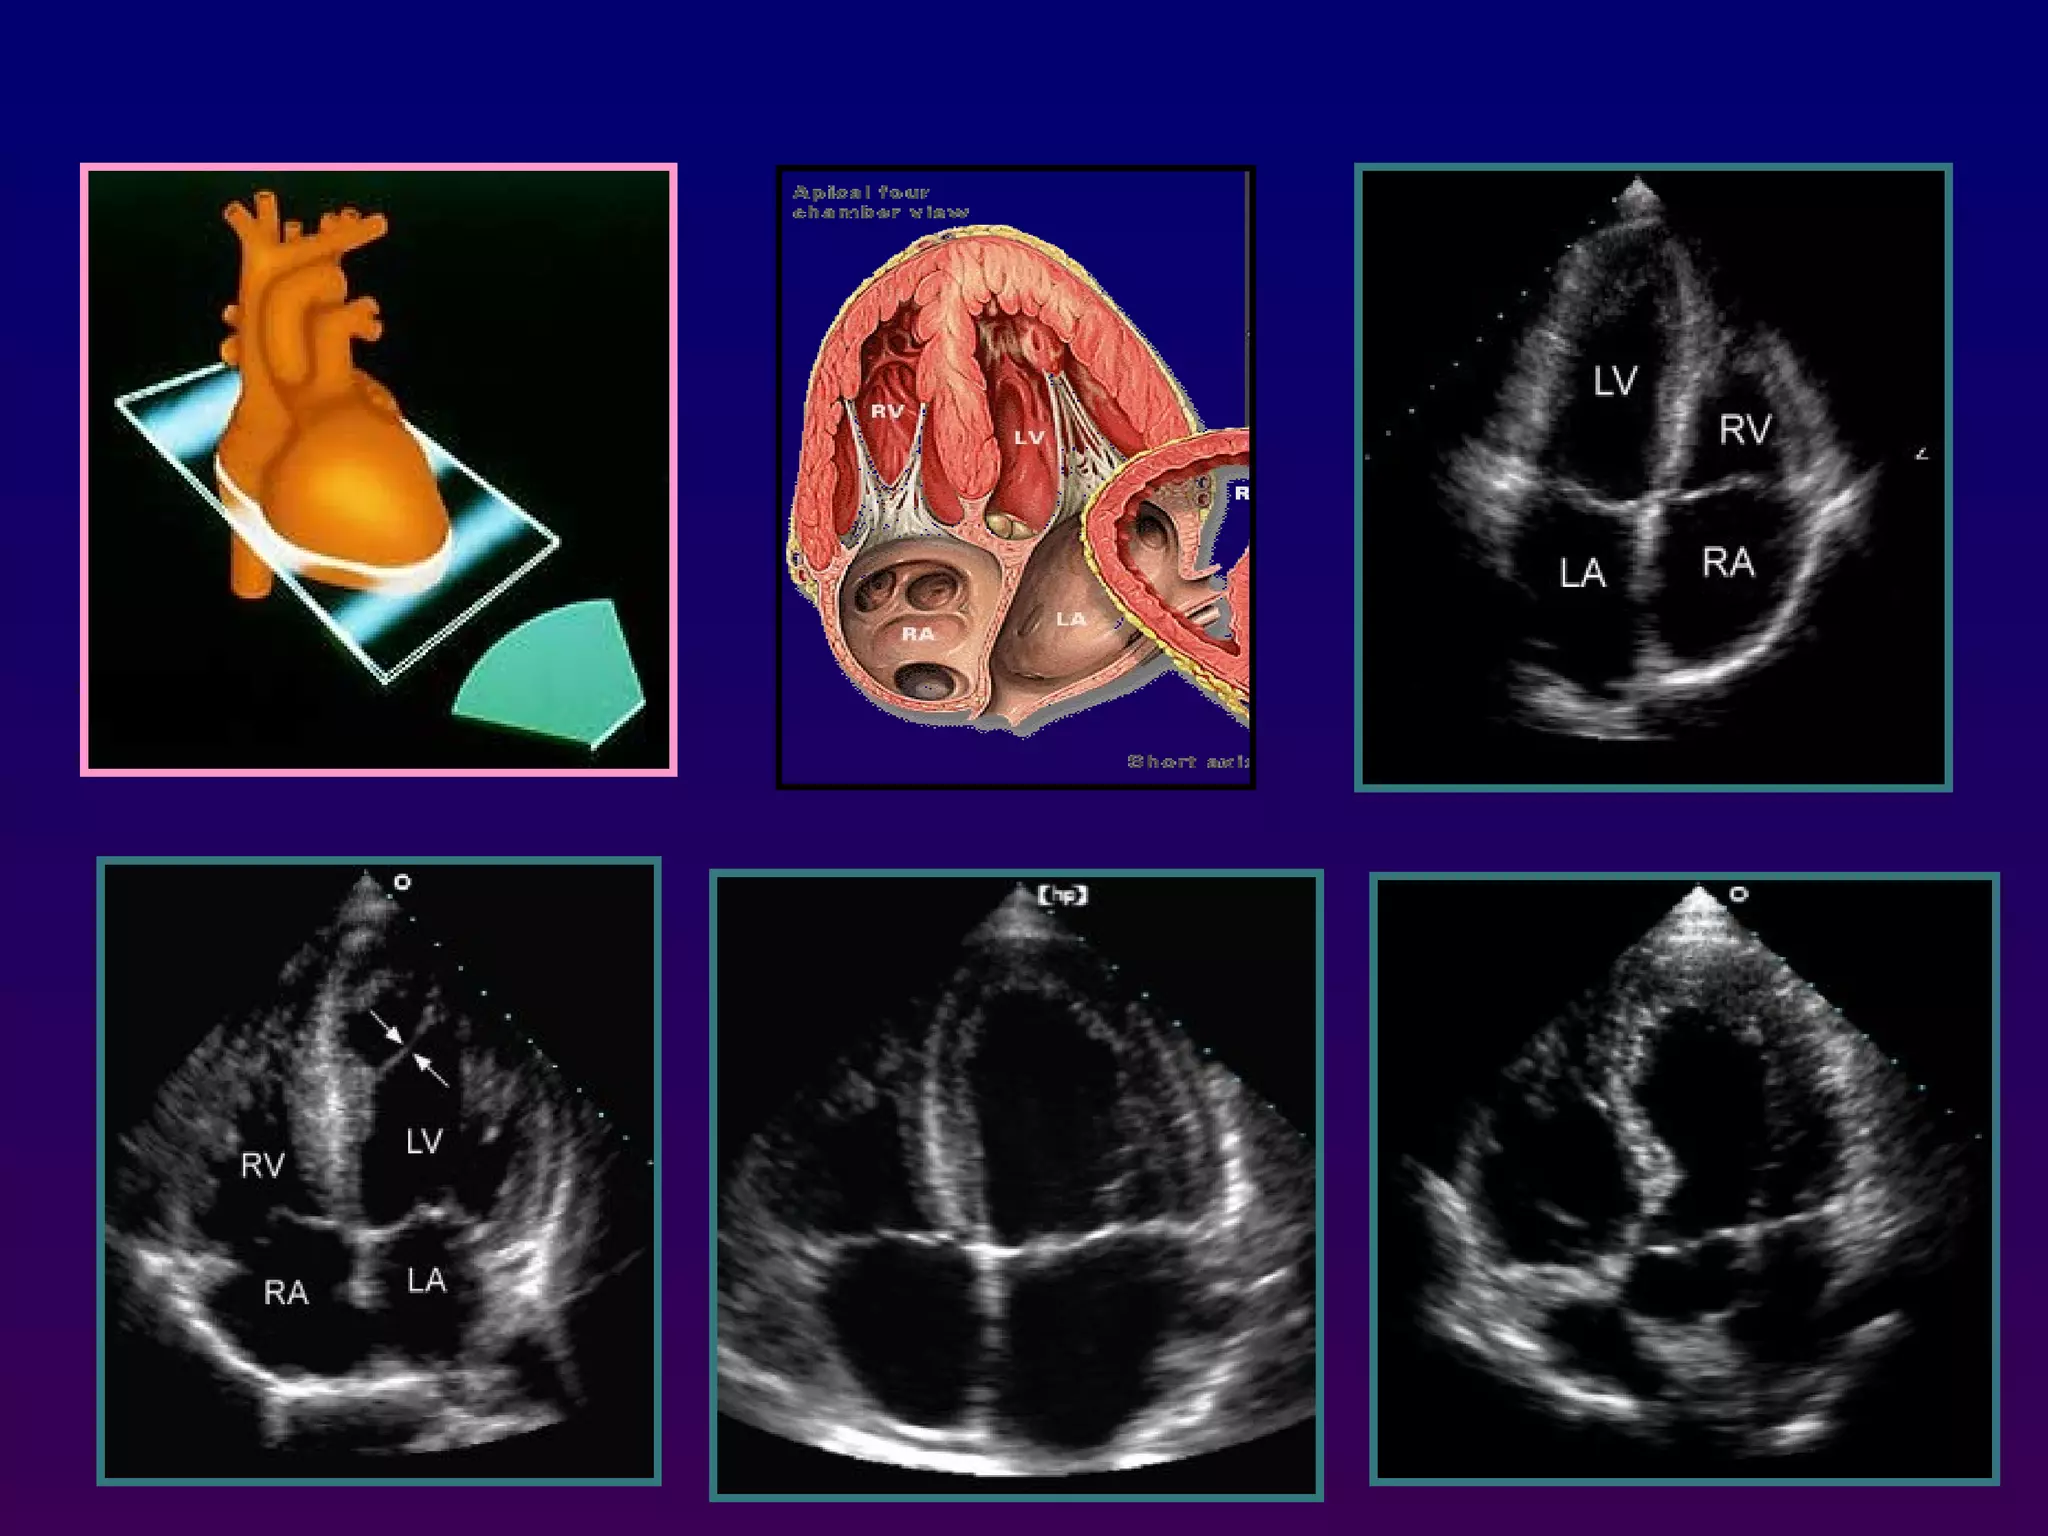

In the apical four-chamber view, all four

chambers of the heart may be seen The left

ventricle appears as a truncated ellipse,RV

triangular with the interventricular septum, apex

formed by LV, and lateral walls visualized.

Apical four-chamber

With the patientmaintained in the left lateral decubitus position, the transducer is placed near the apex of the heart with an inferior orientation In the apical four-chamber view, all four chambers of the heart may be seen The left ventricle appears as a truncated ellipse,RV triangular with the interventricular septum, apex formed by LV, and lateral walls visualized. Apical four-chamber